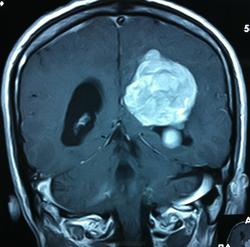

Начало вот здесь http://www.radiomed.ru/cases/kt-gms-obemnoe-obrazovanie-levoi-gemisfery-bolshogo-mozga-vnutrizheludochkovaya-meningioma. Пациент оперирован (меня сначала дезинформировали по поводу операции), перед операцией состояние ухудшилось, возникла правосторонняя гемиплегия, которая осталась и после декомпрессии. МРТ, КТ снимки и выписку предоставила супруга пациента, снимал на iphone, простите за качество, дисков с исследованиями не записывали. Надеюсь вопрос по данному случаю исчерпан.

Вот "цветочки":

И Вы считаете, что эта опухоль имеет интравентрикулярную локализацию?

Изначально по КТ я так предпологал, а теперь на 100% уверен, разве МРТ это не показало? Гистологически - менингиома, опухоль мозговой оболочки. Покажите, пожалуйста, образование где-нибудь прилежит к костям, где есть мозговая оболочка? Я не вижу, зато отчетливо вижу в левом боковом желудочке из оболочек сосудистого сплетения. Что вас еще смущает? По-моему, предостаточно фактов, чтобы развеять все сомнения.

Мне видится так. Иначе в данной локализации просто неоткуда расти оболочечной опухоли. На контрольной КТ, после декомпрессии, когда срединные структуры стали действительно срединны, правое обызвествленное сосудистое сплетение видно отчетливо, а левое, где оно? Ведь если бы образование компремировало, то после операции, когда часть мозга пролабировало в трепанационное отверстие мы бы увидели и левое сосудистое сплетение, но оно интимно связано с образованием и даже "потянулось" за ним в сторону декомпрессионного отверстия, потому что это и есть "росток" откуда выросла опухоль.